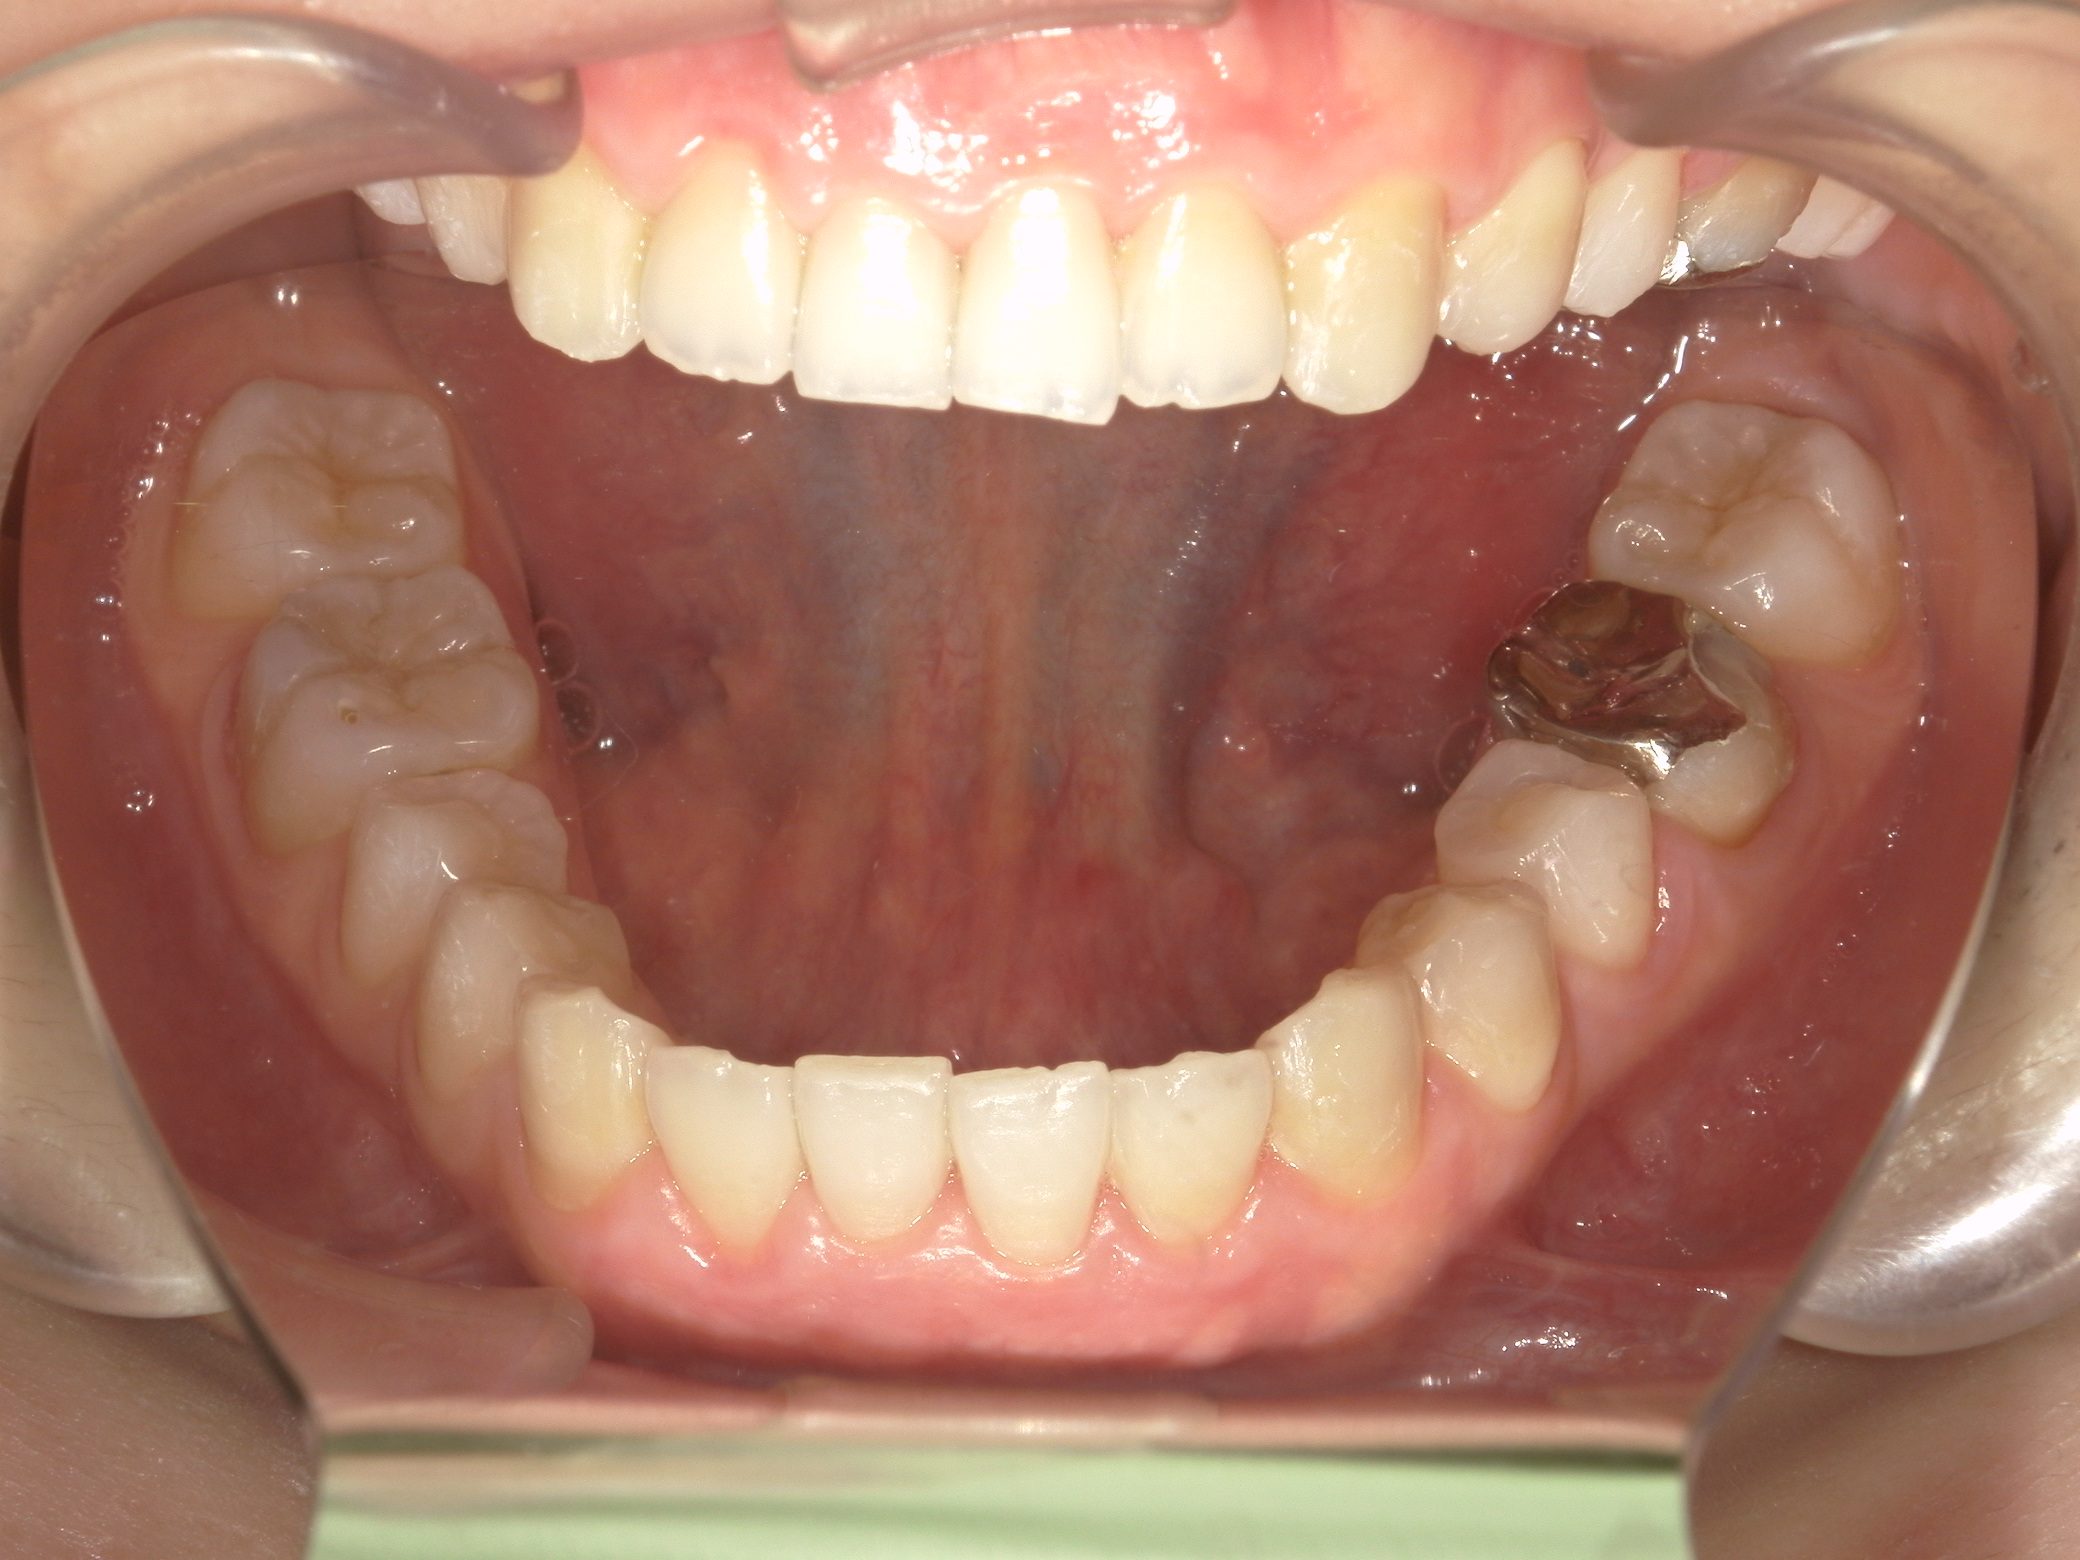

Before

After